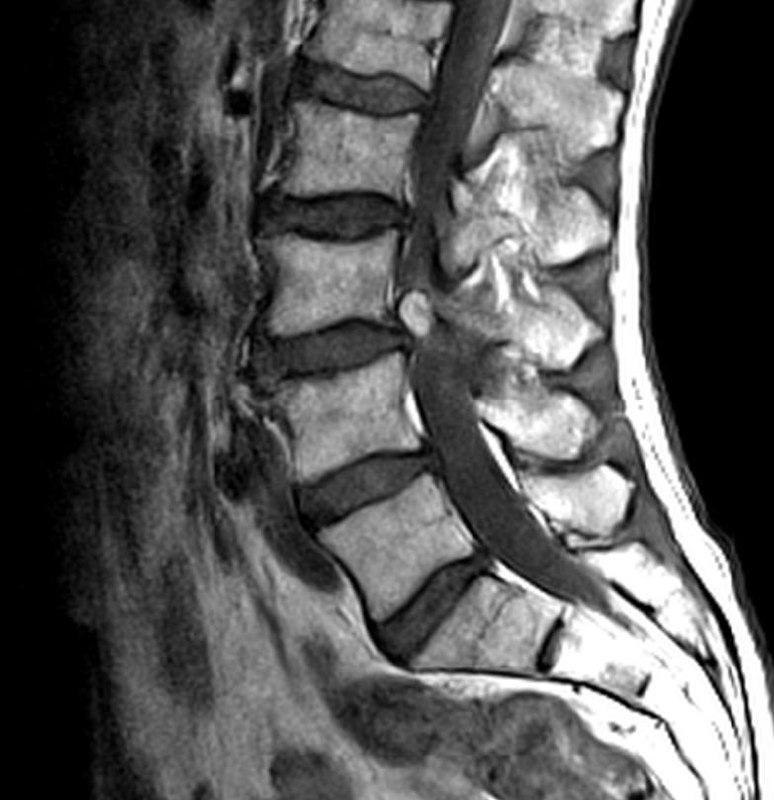

По опыту скажу: когда видишь вот такого, худющего пациента, с таким черным (особенно на Т1, хотя и на Т2, как правило, тоже) костным мозгом, да ещё и со спондилодисцитом, можно не сомневаться, что перед тобой - ВИЧ-инфицированный, и CD4-клеток у него уж точно меньше 150.